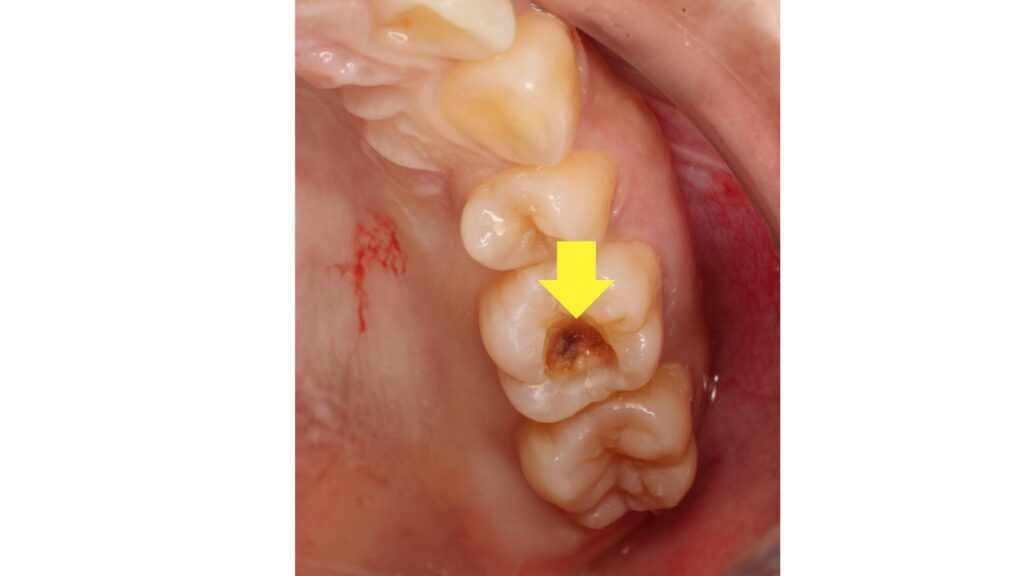

この歯ですが表面的には異常はありません。

しかし怪しい影の原因になっているのは明らかなので、古いプラスチックの詰め物を取ることに。

すると内部にはレントゲンにも映らないように慢性の虫歯が残っていました。

定期健診のレントゲン検査で見つかったものの原因はこれだったのです。